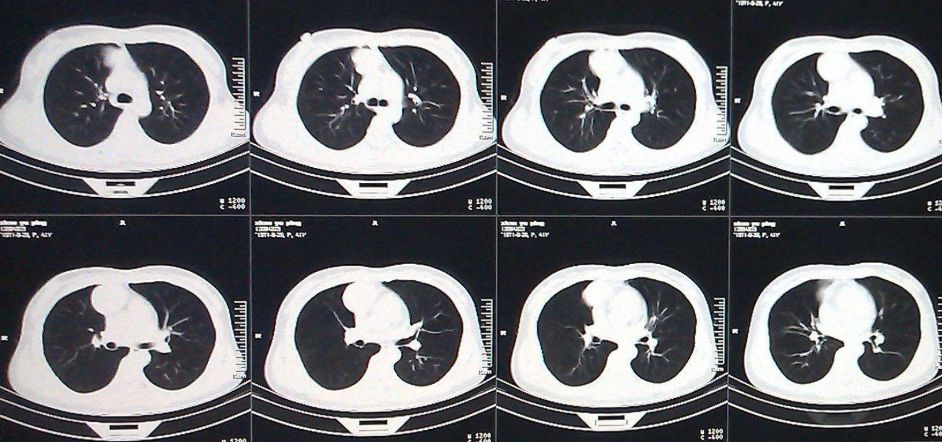

肺结节AI辅助诊断

肺癌,在我国的发病率、死亡率极高,伤害着无数家庭。在我国每年都有近60万人死于肺癌。肺癌防治的重要手段是早期筛查,其中胸部低剂量CT是国际公认的有效手段。而在如今传统的阅片模式中,医学影像面临医疗从业人员短缺,人工分析模式精准度受限,以及基层医院医疗机构诊断水平参差不齐,高年资医生匮乏,易出现漏诊、误诊等问题。

现阶段市场中的人工智能肺CT产品已经实现了肺结节的检出功能,可支持包括:实性结节、磨玻璃结节、形态不规则的大结节、血管旁结节、肺门区结节等。支持提供量化信息检测如自动测量病灶的长径、短径、CT值、体积等参数。支持提供定性信息检测如病灶密度:实性、部分实性、磨玻璃、钙化,以及病灶良恶性等级分类:良性、疑似良性、恶性、疑似恶性。另外支持多种伴随征象的检出,如边界模糊、分叶、毛刺、胸膜牵拉、血管集束等。此外还有肿块、斑片、网影、条索影、气胸、胸腔积液等病变检出。部分产品还含有胸部骨质病变筛查功能,自动检出骨折,支持3D的可视化帮助医生定位,进行全面智能分析与诊断。

很多创业公司都研发了肺部CT检测相关产品,此类产品也是国内医学影像创业公司的门槛产品。该方向起源于国际LIDC以及LUNA的肺结节检出竞赛。目前,各个公司推出了他们的相关产品。例如,深睿医疗(DeepWise)推出的Dr.WISE CAD医疗影像诊断系统;推想科技(Infervision)的InferReadCTLung产品系统;依图医疗(YITU)、图玛深维(12Sigma)、医准智能(MEDICAL AI)等公司的产品,均已经在市场上投入使用。上市公司方面,阿里健康研发的医疗AI产品“Doctor You”已经公开发布,此外还有科大讯飞、中国平安集团旗下平安科技、腾讯觅影等。

在国外,具有代表性的有谷歌的深度思维(DeepMind,美国)、西门子(SIEMENS,德国)、飞利浦(PHILIPS,荷兰)、ARTERYS、通用电气(GE,美国)等公司研发的相关产品,均可以支持病灶筛查、定位、定量标注、诊断等一系列阅片流程,从而推进精准医疗建设,优化病患就医体验。